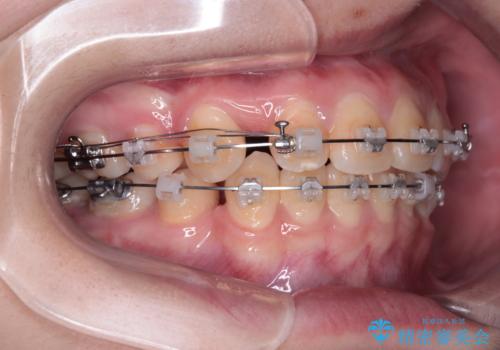

- 矯正装置

- クリアブラケット

- 転勤により東京へ移られることになり転院先を探されていた患者様です。ワイヤー矯正の途中での急な転勤なうえ、今後2~3年以内に再度転勤になる可能性もあるというご事情でした。

そのため、限られた期間内に効率よく治療を完了するために、「抜歯スペースの確実な閉鎖」「深い噛み合わせ(過蓋咬合)の改善」の2点を主軸とした治療計画を立てました。

結果的に1年半で、再度転勤になる前に治療を終えることができました。